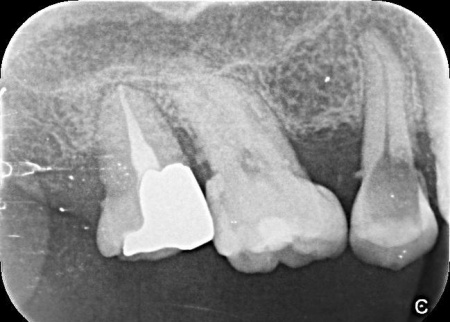

50代女性銀歯の下の虫歯を除去しセラミックで修復したケース

レントゲン像で金属の下に虫歯があり、患者さんは入れ替えを強く希望されました。

特に審美的な要求をされたため、セラミック修復の説明をし、治療の同意を得ました。